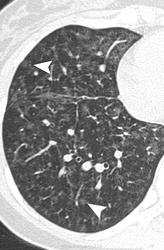

Легочная вено - окклюзионная болезнь (ЛВОБ)- редкое заболевание не установленной этиологии, при котором развитие и прогрессирование ЛГ связано с поражением мелких легочных вен и венул, в том числе тромботического характера.

Ранее ЛВОБ рассматривалась как подтип первичной легочной гипертензии (ПЛГ), однако с учетом вероятных различий в патогенезе ЛВОБ и лечении ПЛГ, в 1998г. ЛВОБ была включена в категорию легочной венозной гипертензии наряду с заболеваниями левых отделов сердца, компрессией легочных вен, фиброзирующим медиастинитом. В 2003г. на 3-м Мировом симпозиуме по ЛГ в Венеции (Италия) на основании сходных патоморфологических проявлений, клинической картины и возможного развития отека легких при назначении простагландинов ЛВОБ и легочный капиллярный гемангиоматоз- доброкачественное неметастазирующее сосудистое образование, приводящее к развитию ЛГ- были объединены в один подтип клинического класса легочной артериальной гипертензии.

Легочный капиллярный гемангиоматоз